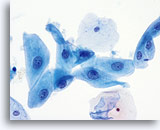

No diagnostic classification causes more debate than Atypical Squamous Cells (ASC). New terms rose from the revised classification of The Bethesda System (TBS) in 2001 and remain for TBS 2014. TBS indicates that the ASC category should be the diagnostic consideration when squamous abnormalities are present that are more marked than those attributable to reactive changes, but fall qualitatively or quantitatively short of the diagnostic criteria for a low grade or high grade squamous intraepithelial lesion. Furthermore, TBS stresses the importance of qualifying this diagnosis as “undetermined significance” (ASC-US) or “cannot exclude HSIL.” (ASC-H)

The proper classification of ASC challenges the cytotechnologist and pathologist and, writing any chapter describing the morphologic criteria of ASC is challenging, given the subjectivity of this interpretation. Since the adoption of TBS, laboratory professionals interpreting the conventional Pap smear may have used this category as a “catch all” for smears that are difficult to classify.

Artifacts inherent to the conventional Pap smear, such as air-dried or partially obscured cells, may result in an ASC diagnosis. The degree of apparent atypia in reactive cells may also be exaggerated by air-drying or smearing. These issues result in the artifacts that make it difficult for the cytotechnologist and pathologist to adequately visualize the nuclear detail of the cells in question, resulting in a less than definitive diagnosis.

The immediate wet fixation that is used in the ThinPrep process may allow the pathologist and cytotechnologist to move away from the ASC “catch all” and better differentiate between cellular changes due to reactive conditions, definitive squamous atypia, and dysplastic lesions. This is not to say that ASC interpretations are eliminated by the adoption of the ThinPrep Pap Test, but the laboratory staff has the opportunity to refine their morphologic criteria, eliminating certain “ASC” cases arising from poor preparation, and better identifying cases that may

harbor abnormality.

The ThinPrep Pap Test® minimizes the troublesome artifacts inherent in smear and spray fixation. This allows for

the nucleus to be adequately visualized facilitating a more definitive diagnosis. The epithelial cells that are generally incorporated in the ASC category are the mature squamous and squamous metaplastic cells exhibiting changes that are minimal and fall short of a diagnosis of LSIL or HSIL. The nuclei are slightly enlarged and this enlargement is compared to the normal entity of the same cell type. The nuclei may show slight nuclear membrane irregularities but are more often smooth. When dealing with the metaplastic component, one needs to make sure that the irregularities aren’t due to a vacuole(s) pushing the nucleus into the aberrant shape. The chromatin pattern is finely granular and evenly distributed. Chromocenters or nucleoli are generally inconspicuous or absent unless a reactive process is occurring in conjunction with the atypia at which point the differential diagnosis of reactive needs to be considered depending upon the presence or lack of the other criteria.

With either conventional or ThinPrep® slides, an ASC interpretation may arise from any of several different cellular changes, including but not limited to, squamous atypia, atypical squamous metaplasia, and atypical parakeratosis. The criteria for ASC on the ThinPrep Pap Test are as follows:

| REACTIVE | ASC-US | LSIL | |

| Nucleus | Enlarged 1.5-2 times,flat | Enlarged 2 -3 times, flat to minimal depth of focus | Enlarged 3-4 times,Slight depth of focus |

| Nuclear Membrane | Smooth | Smooth to slightly irregular | Smooth to slightly irregular |

| Chromatin | Finely granular, evenly distributed | Finely granular, evenly distributed | Slightly more granular, evenly distributed |

| Nucleoli/Chromocenters | Small to conspicuous, sometimes multiple | Inconspicuous or absent | Absent |

| Cytoplasmic Features | Peri-nuclear halos present | Questionable cavitations | Diagnostic HPV cavitations |

| Bichromasia | Can be present | Not present | Not present |

The images that follow are ThinPrep® Pap Test specimens that reasonably could be interpreted as reactive changes,

ASC-US, and LSIL.